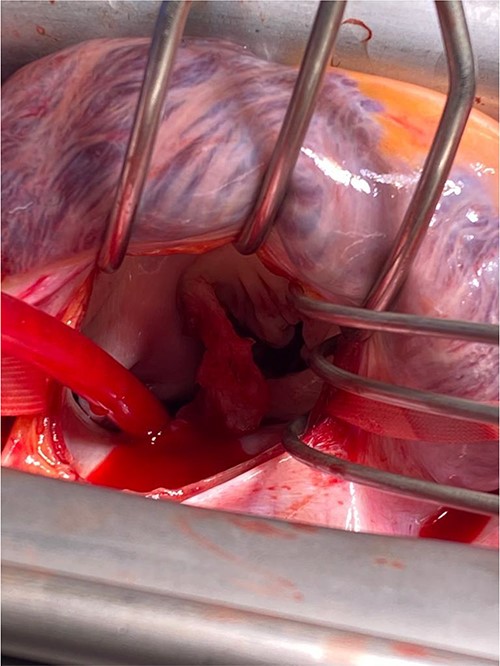

Intra-operatively, femoral–femoral bypass was established and a 3 cm windsock vegetation was found with a 1.5 × 1.5 cm hole at the aortic inlet on the annular junction. The vegetation travelled from the LV to LA as shown in Figs 3 and 4. The vegetation was excised and the valve debrided, which resulted in moderate regurgitation from severe. Hence, a further 26 mm Physio II ring was placed resulting in no mitral regurgitation. The excised vegetation is shown in Fig. 5 and the post-op TTE images are shown in Figs 6 and 7.